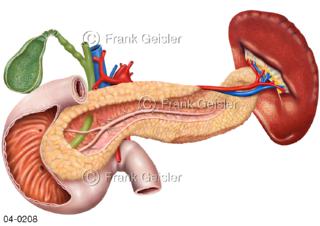

Bildergalerie Topografie Organe

Bilder zur topografischen Anatomie, die Lage der Organe und die Strukturen nach ihren räumlichen Lagebeziehungen zueinander, Übersicht der inneren Organe im Kopf und im Rumpf, Topografie der Organe im Brustraum (Thorax) und im Bauchraum (Abdomen)